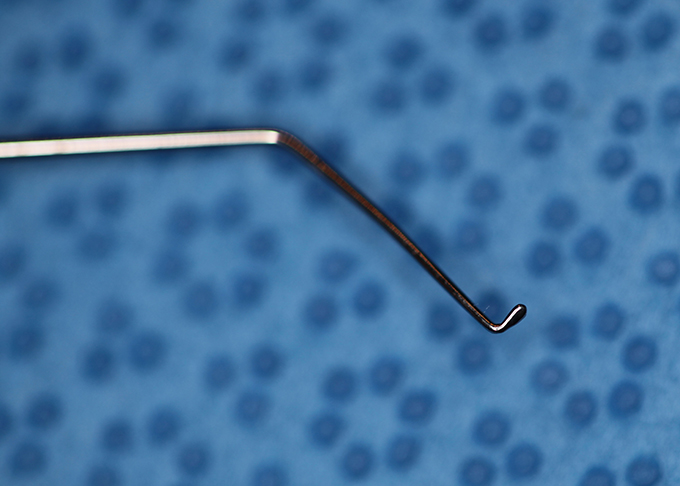

Kuglen Hook, straight, round handle

Kuglen

Catalog: Katena K3-5522

Typical Use(s): Position IOL and haptics; Fix eye with paracentesis; Retrieve suture from AC

Kuglen Hook, straight, round handle (Enlarged)

Kuglen

Catalog: Katena K3-5522

Typical Use(s): Position IOL and haptics; Fix eye with paracentesis; Retrieve suture from AC